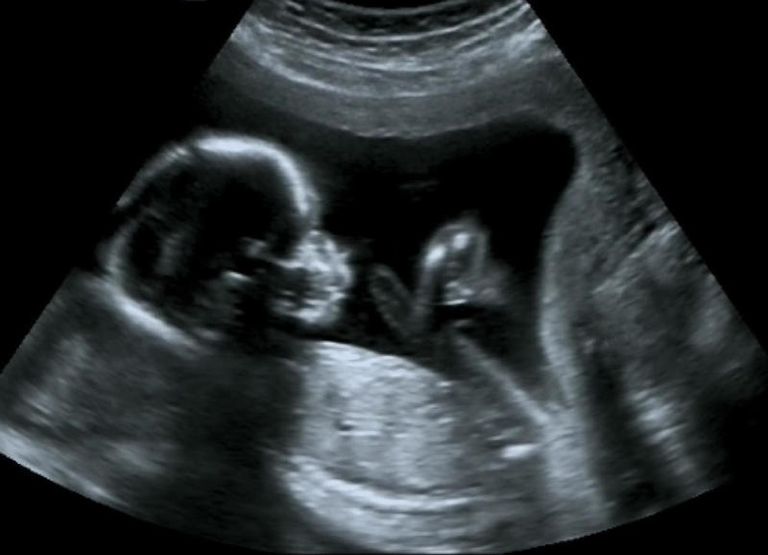

4- المتابعة بالأشعة التلفزيونية

خلال رحلة الحمل التي تستغرق 9 أشهر، يعد اليوم المحدد للأشعة التلفزيونية على الجنين بمثابة لقاء بين الأم وطفلها، فهي تعطي نفسها طاقة وأملا لتحمل مشقات الحمل على أمل لقاء قادم، وهي أهم وسائل الاطمئنان على الأم وطفلها.